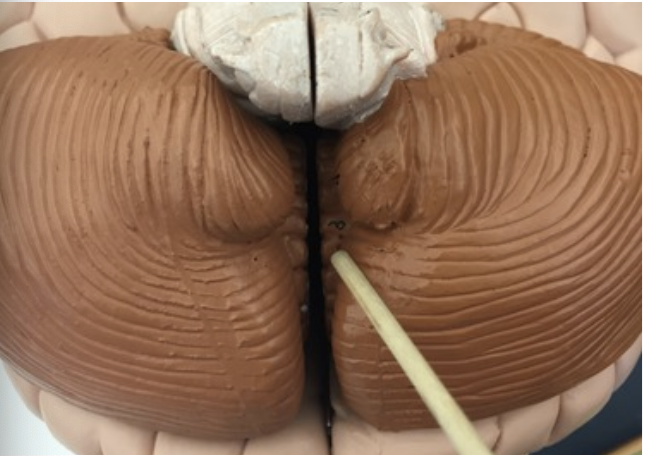

what are the folds in the cerebellum called?

Folia